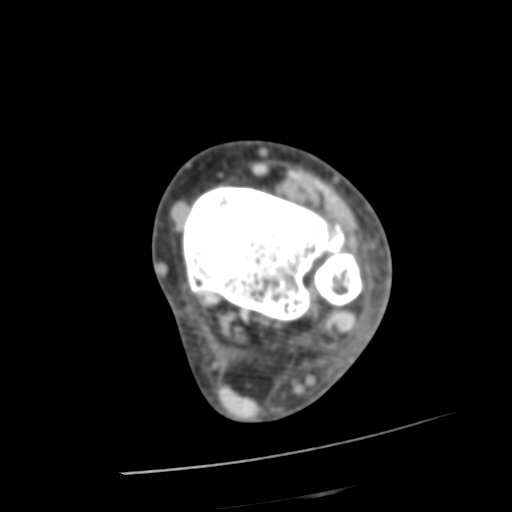

CT : avulsion fracture of distal tibia at distal tibiofibulat ligament insertion.